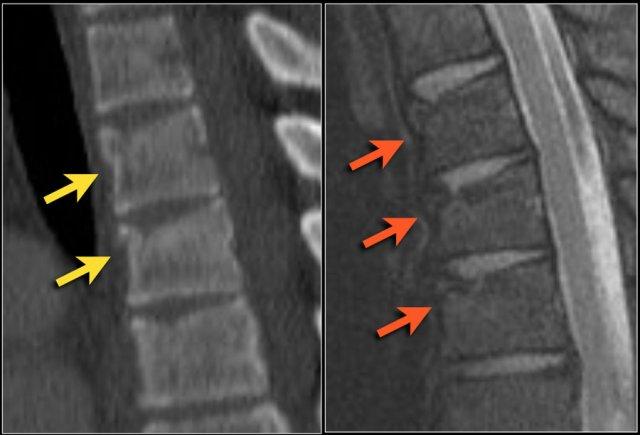

Rất thường gặp trường hợp CT và MRI phát hiện nhiều ổ gãy xương hơn so với X-quang thường quy.

Trong trường hợp này, CT phát hiện 2 ổ gãy và MRI phát hiện 3 ổ gãy.